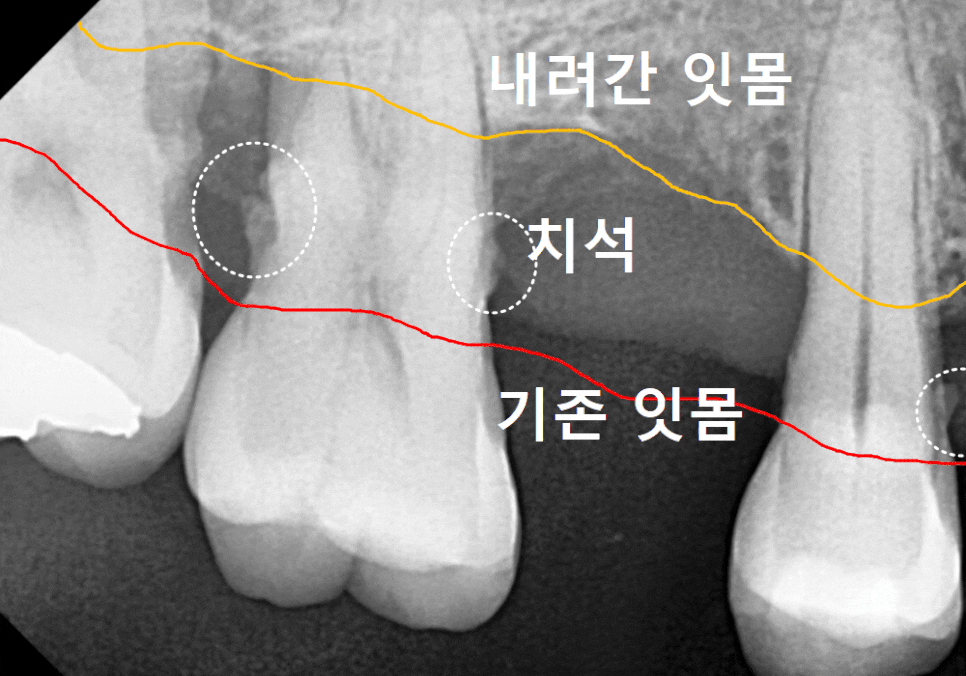

치은연하치석의 위험성

눈에 보이는 치석보다 더 무서운 것이

바로 잇몸 라인 아래쪽에 숨어있는

'치은연하치석'이에요.

이 치석들은 잇몸 깊숙한 곳에 자리 잡아

점점 잇몸뼈를 녹입니다.

이렇게 잇몸 안쪽까지 파고든 치석은

치아를 지탱하는 힘을 약화시켜

결국 멀쩡해 보이던 치아를 흔들리게 만듭니다.

더 큰 문제는 깊이 박힌 치석의 경우,,

일반적인 스케일링 기구만으로는

뿌리 끝까지 닿기가 어렵다는 점이에요.

매끈해보여야 할 치아 뿌리 쪽에

돌기처럼 무언가 붙어있는게 보이시나요?

바로 치석인데요.

그런데 만약 엑스레이 사진에서

이처럼 치아 옆면이 매끄럽지 않고

돌기처럼 튀어나온 것이 보인다면,

정상적인 잇몸 상태 , 치아 뿌리 면이 매끄러움

치은연하치석이 뿌리면에 돌기처럼 붙어있는 모습

그건 치석이 이미 엄청나게

두껍고 단단하게 쌓였다는 뜻이에요..ㅜㅜ